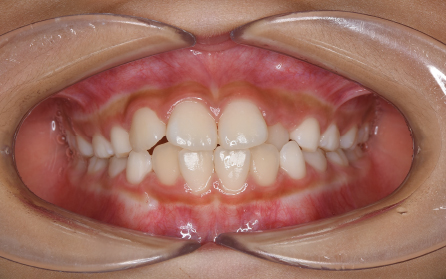

19歳 女性

主訴 「前歯のでこぼこを治したい」

診断 「両側側切歯のクロスバイトを伴う叢生症例」

上下前歯部の叢生の改善のため、歯と歯の間を0.5mm程度削ってスペースを確保しながら歯を並べました。患者さんの協力(マウスピースの使用状況等)も良好で、前歯が前方に突出することなく側切歯(2番目の歯)のクロスバイトも改善されました。前歯が突出しないように治療計画をたてないと口唇が閉じにくくなったり、口元がもっこりしてしまいます。治療期間は18か月でしたが、動的治療後は歯を安定させるために保定装置の使用が必要です(最低2年)。矯正治療では患者さんの協力が非常に重要であり(特にマウスピース矯正の場合は使用時間)、治療結果や治療期間に影響します。また、歯の移動にはワイヤー矯正、マウスピース矯正にかかわらず歯根吸収、歯肉退縮、歯髄壊死のリスクがあります。